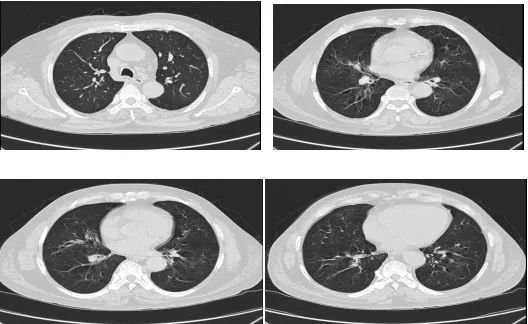

莫大爷(化名),60岁,平日身体健朗,一个月前突发呼吸困难到我院呼吸与危重症医学科就诊。入院时端坐呼吸,两肺可闻及大量哮鸣音,根据症状及检查结果,专家考虑为哮喘急性发作,按照哮喘急性发作给予相关处理,经过治疗呼吸困难程度暂时减轻,但是夜间气喘发作依然频繁。

既然是哮喘,按照哮喘的常规治疗,症状应该得到及时控制才对,为什么夜间气喘还是没能控制呢?看着莫大爷痛苦的样子,专家团队很是着急。为了尽快找到病因,及时解除莫大爷的痛苦,呼吸与危重症医学科三区感染学组专家团队立即组织召开专题疑难病例讨论会,经过认真细致的讨论和研究,专家们根据以往的临床经验大胆猜想:莫非莫大爷患的是变应性支气管肺曲霉菌病?